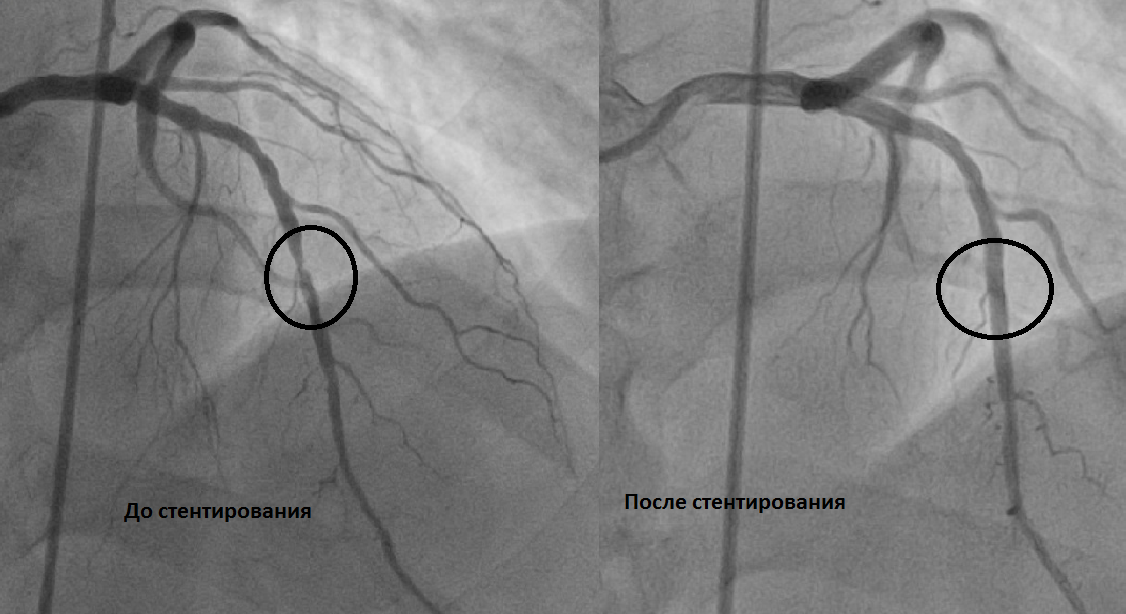

Начнём с терминов. Стентирование - это чрескожное коронарное вмешательство, ЧКВ. Малотравматичная операция, когда через пунктированную артерию (всё реже - бедренную, в основном - лучевую) благодаря применению катетерных технологий подбираются к стенозу и "раздувают" изнутри артерию в месте стеноза, а потом устанавливают в этот участок стент - ажурный, но прочный каркас из металла, покрытого лекарством.

ЧКВ идеально подходит там, где анатомия коронарных артерий проста. Один-два значимых стеноза, не слишком извитые сосуды, невысокий SYNTAX-балл (отражает тяжесть атеросклеротического поражения коронарного русла и техническую сложность восстановления кровотока) - и стент решает проблему быстро, малотравматично и эффективно. Именно поэтому при остром инфаркте миокарда первичное ЧКВ остаётся методом выбора.